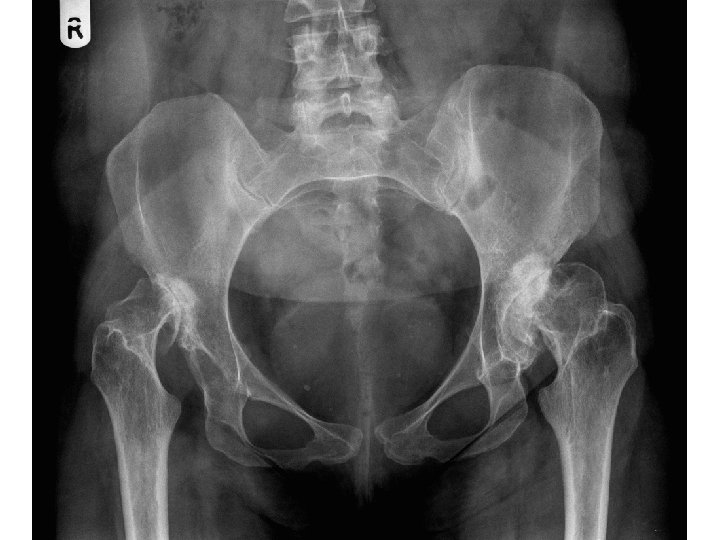

Perkins Hilgenreiner

Acetabular Index